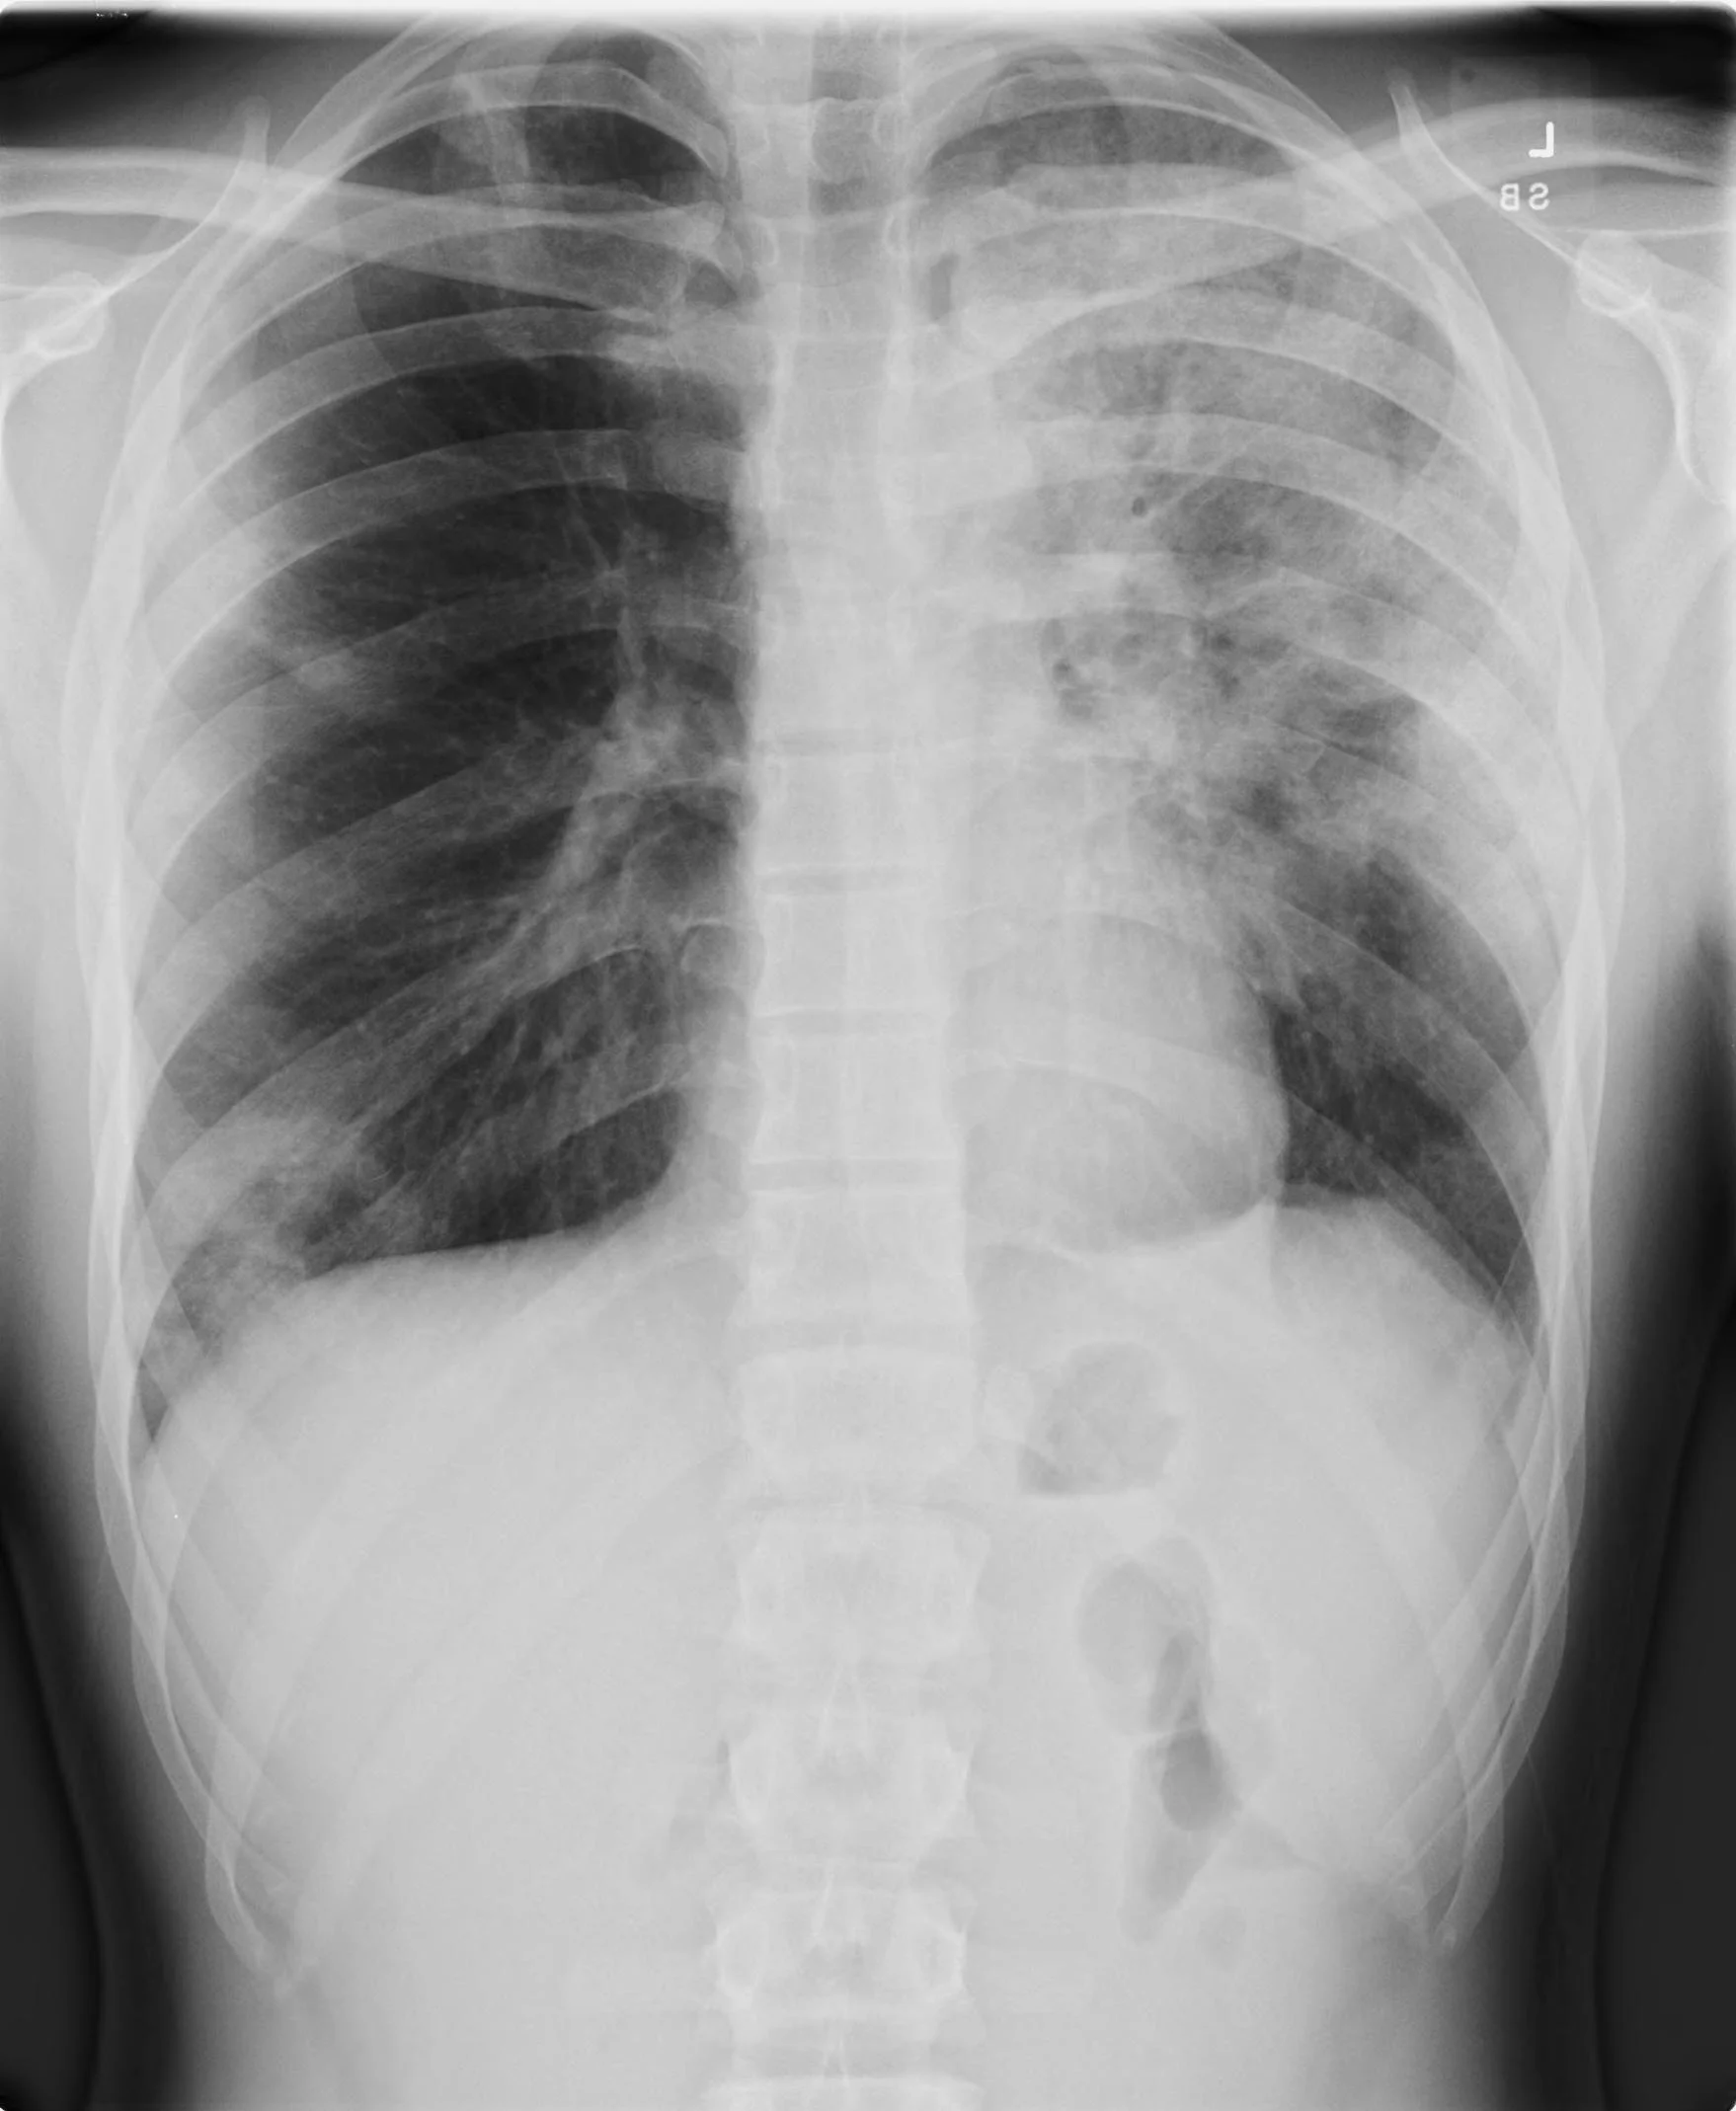

This weeks grand rounds started off with our Morbidity and Mortality conference led by Dr. Shaw who led us on an education expedition covering the use of REBOA, surgical vs. medical management in spontaneous miscarriage, ways we can improve our use of the electronic medical record, management of a persistent air leak in a patient with a chest tube, and the role of CT in CAP. Dr. Alwan then provided us an in-depth look at the often untold challenges of life as a refugee as well as the challenges we face in providing care for these patients. This was followed by Dr. Randolph who presented a case of an incredibly complicated patient with a pulmonary embolism to highlight the steps in management of a decompensating patient with a pulmonary embolism before you initiate thrombolysis. Next up was Dr. Gottula and Dr. Hinckley who went head to head with a challenging presentation of acute aortic dissection as part of our CPC lecture series. Dr. Leech then finished up the day with a case based discussion on the utility of the Kocher Criteria in the evaluation of child with an acutely painful hip.